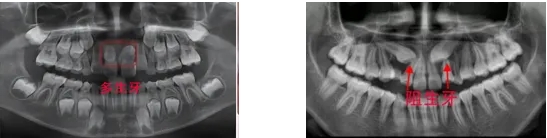

5、多生牙、阻生牙

前者會影響正常牙的萌出,位置排列,壓迫正常牙的牙根導(dǎo)致牙根吸收。后者也有可能造成鄰牙牙根的吸收。如發(fā)現(xiàn)孩子口內(nèi)牙齒數(shù)目異常,請及時帶孩子就醫(yī)檢查,早發(fā)現(xiàn)早治療。